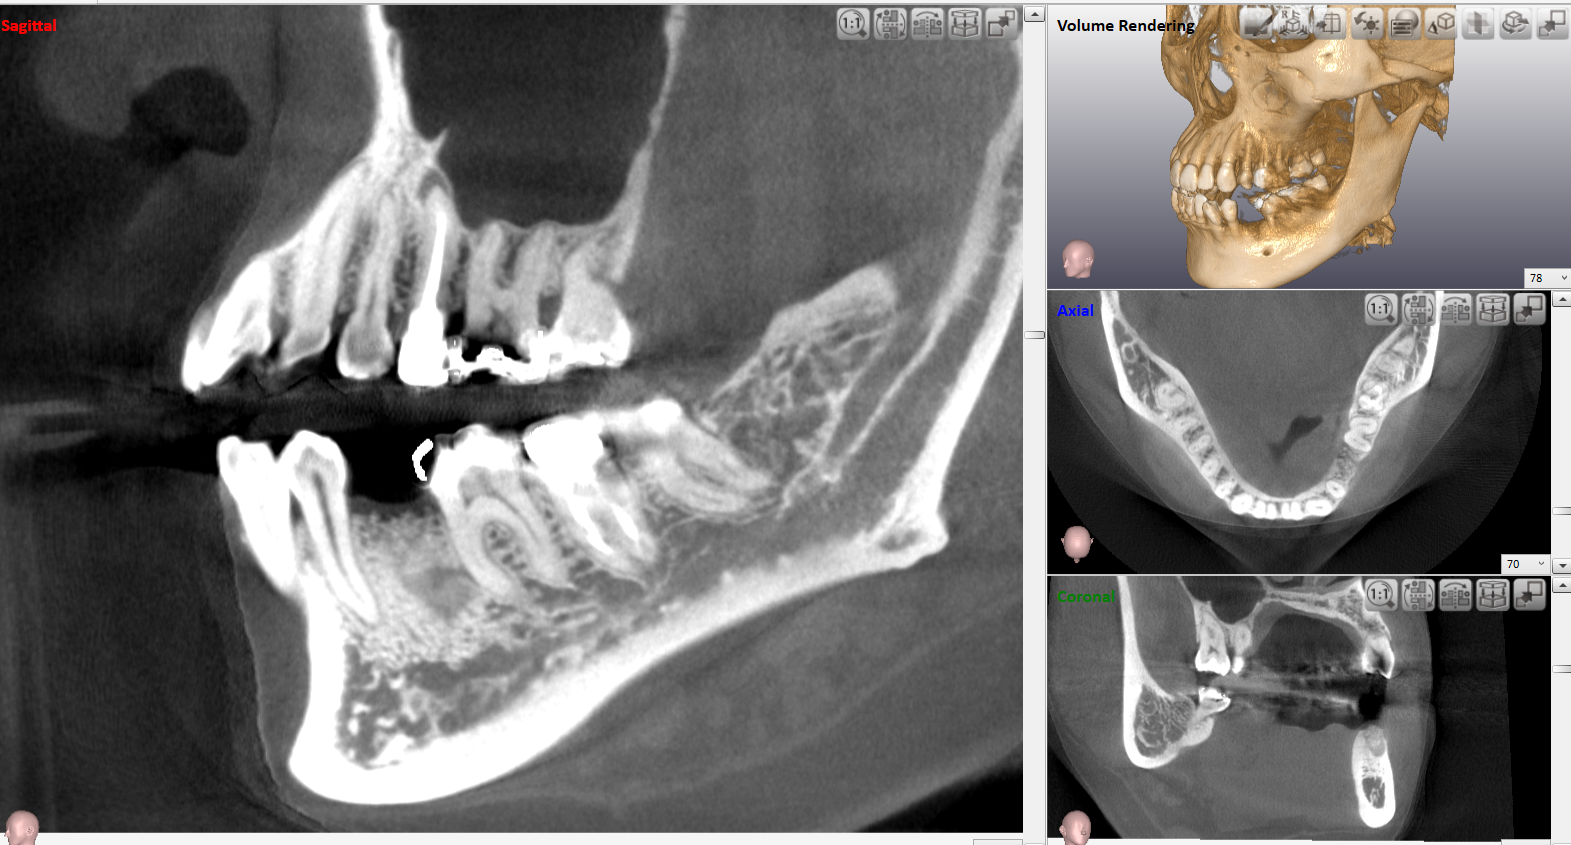

③歯科用CT・レントゲン診査

精密検査ができる歯科用CTおよびレントゲンを用いてお口の中を撮影し、肉眼では見えない顎骨や周囲の歯の状態を診ていきます。

ここで顎骨の量や神経との位置関係などを確認致します。